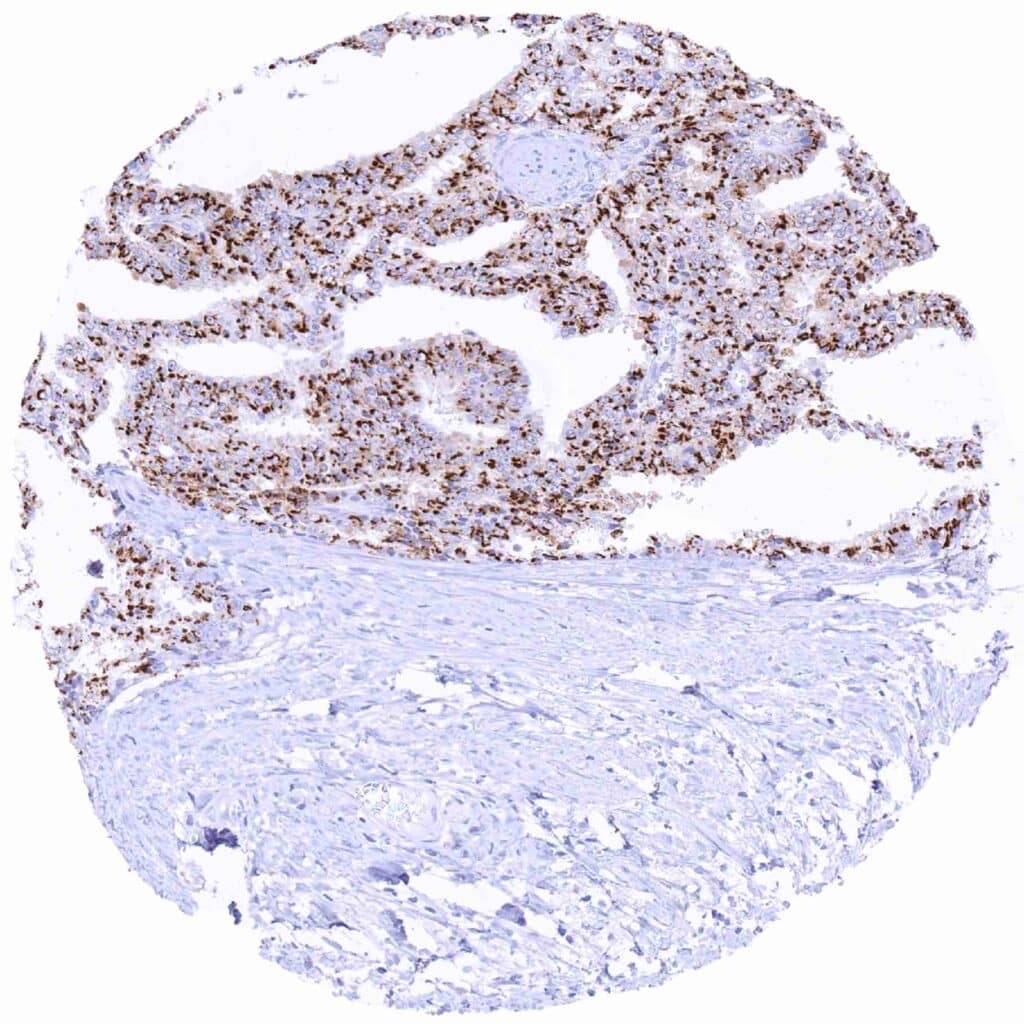

Prostate – Adenocarcinoma (Gleason 3+3=6) with strong Prostein immunostaining of tumor cells